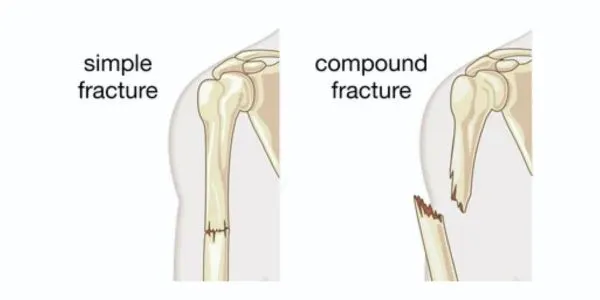

Bone injuries can feel overwhelming and hard to understand when trying to figure out the differences between types of fractures. If you’ve …